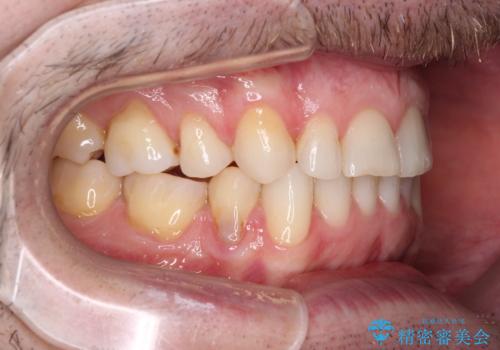

- 上下前歯の叢生を気にして来院された患者様です。

抜歯矯正をした後戻りということで、歯列不正はそれほど大きくなかったため、インビザライン・ライトを用いて矯正治療を行うこととしました。

前歯のデコボコが残っており、シミュレーション通りに動いていない部分がありましたが、再矯正であることやご本人の満足いくところまでデコボコが改善されたとのことで、治療を終了することとしました。